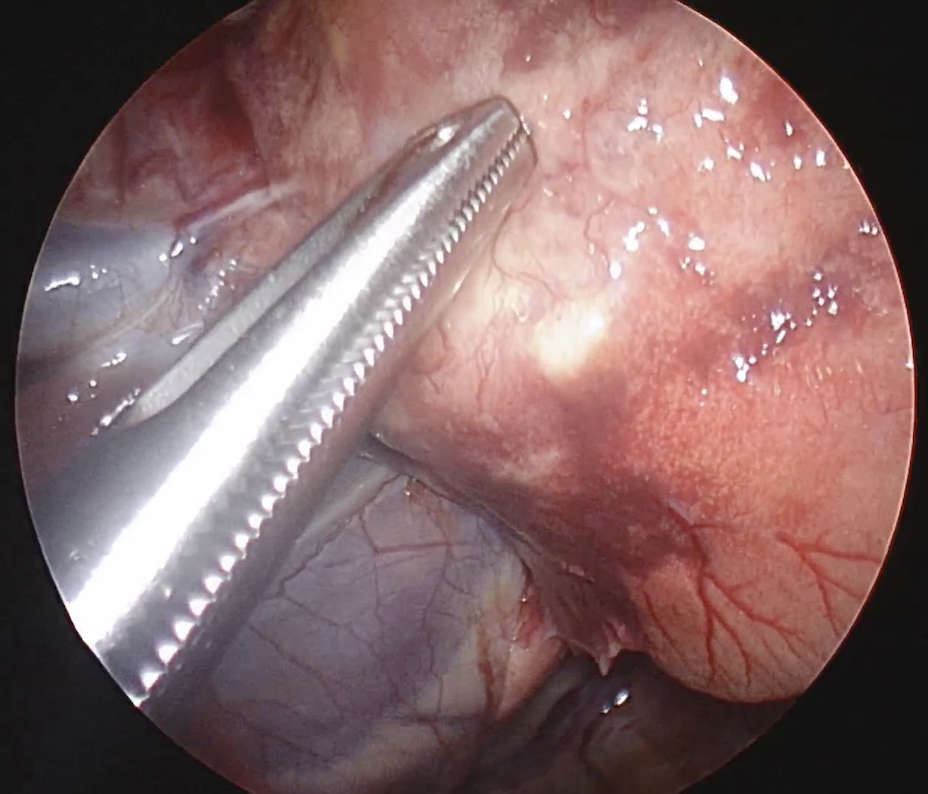

以下は手術の写真になります。

胸の中に鉗子を入れているところ

切除のために止血クリップを設置しているところ

また拡大する映像を見ながらの手術なので安全性も高いです。